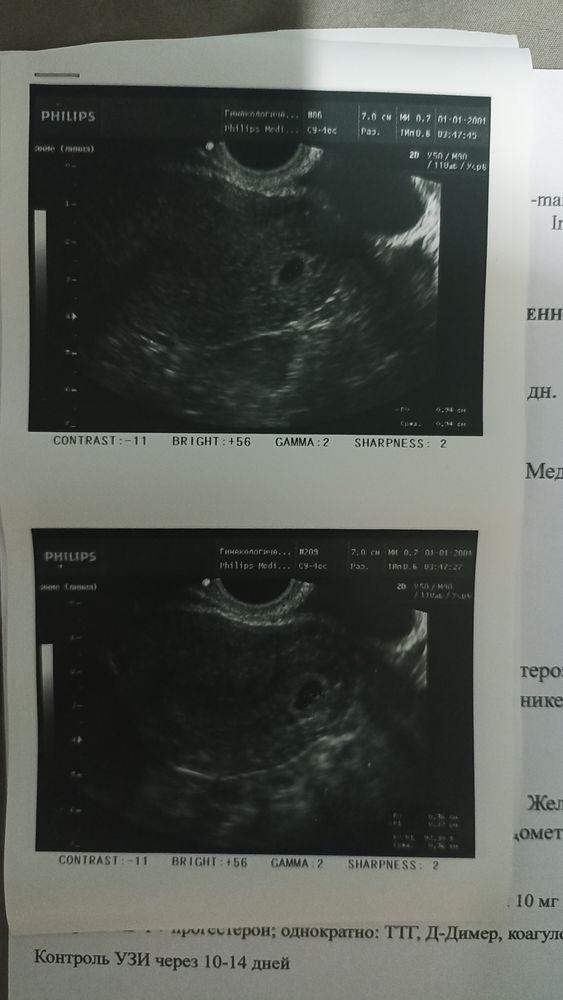

Первое знакомство с нашей икриночкой✨

Всё-таки исходя из анамнеза был назначен Дюфастон. Спорить с врачом не буду. Надо, значит надо. Назначила из-за зб в анамнезе и эндометриоза. Ещё почему-то сказала дальше мониторить ХГЧ и прогестерон. Если последний начнет снижаться, добавить ещё 1 тб Дюфастона. Сейчас сказала всё замечательно, уже записалась на следующее УЗИ))